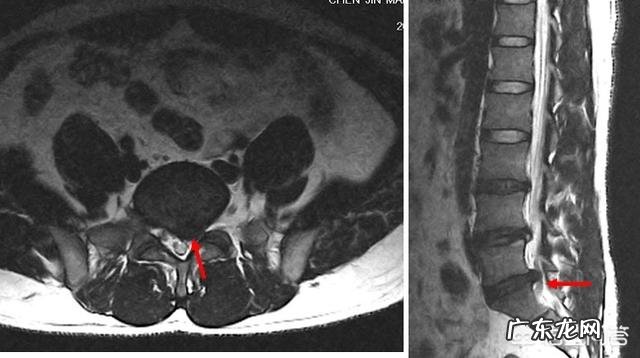

1.L5-S1椎间盘突出症

症状基本和LL4-5疼痛特点是一致的 , 例如咳嗽打喷嚏痛 , 半夜痛醒 , 但是疼痛出现部位不一样 , 在臀部后侧腿后侧 。

2.梨状肌综合征

早晨起来疼痛 , 这个多表现在弯腰穿鞋子、穿裤子费事 , 站起来也不怎么痛 , 咳嗽打喷嚏不疼 , 坐硬的东西痛感明显 。